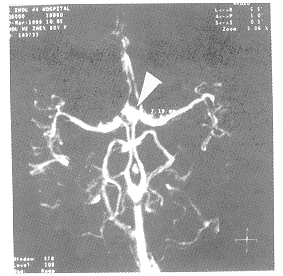

图4

图5

图6

图4、5、6箭号所指为前交通动脉动脉瘤